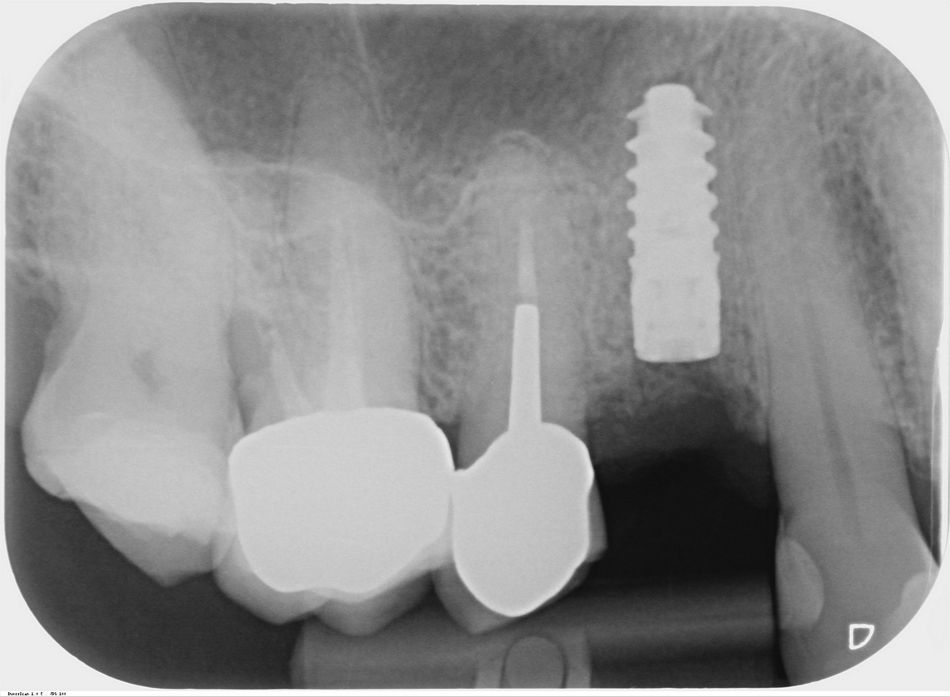

The radiographic evaluation showed moderate interproximal vertical and horizontal bone loss (Fig. 1).

Peri-implantitis on #14 was diagnosed on the basis of the clinical and radiographic findings. The treatment plan started with etiological treatment and included the elimination of the focus of infection. A small incision was made in the abscess area. The lesion was rinsed with povidone-iodine and chlorhexidine and covered with a gauze containing oxytetracycline and hydrocortisone. Then, the crown was unscrewed and gutta-percha inserted into the pocket. This was x-rayed to confirm the origin of the lesion. This assessment confirmed that the focus of infection was located on the buccal region and associated with implant #14. (Fig. 2)